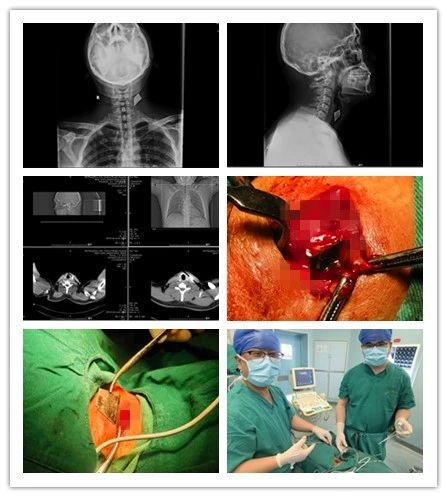

患者,男,35歲,3個(gè)月前頸部被銳器刺傷,傷后出血量約50ml,伴有疼痛,不伴有麻木,呼吸正常,于外院行清創(chuàng)縫合手術(shù),術(shù)后切口反復(fù)感染,并伴有頸部及左側(cè)上肢放射性疼痛,后于我院復(fù)查頸部正側(cè)位片示左側(cè)頸前不規(guī)則致密影,門(mén)診以“左頸部異物”收入院。

乳腺甲狀腺外科王思雷和楊汶士主治醫(yī)師接診后,追問(wèn)患者病史并仔細(xì)檢查,確認(rèn)患者皮膚淺層不存在異物,認(rèn)為異物存在于頸深部,且異物為銳器“美工刀片”,有傷及頸部大血管及氣管、食管可能,隨時(shí)危機(jī)生命,建議手術(shù)取出。但異物位置深,緊鄰頸部大血管、氣管、食管,存在較大手術(shù)難度和風(fēng)險(xiǎn)??浦魅卫罘搴屯跛祭住钽胧恐髦吾t(yī)師進(jìn)行充分術(shù)前討論后,制定了周密的手術(shù)方案,在彩超及C臂機(jī)引導(dǎo)下,精確定位,為患者施行頸部異物取出術(shù)+清創(chuàng)縫合術(shù)。術(shù)中發(fā)現(xiàn)異物為銳器“美工刀片”,刀刃鋒利,位置深達(dá)頸椎前側(cè),緊鄰頸部大血管及氣管、食管,差之毫厘便可能造成血管破裂致大出血。兩位醫(yī)師憑借嫻熟的技術(shù),小心翼翼探查,僅用十分鐘便成功取出異物。